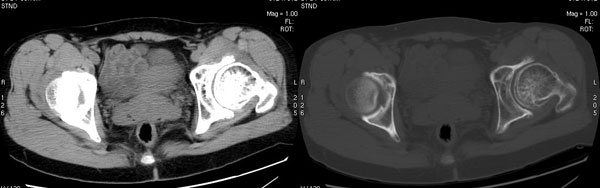

以下是引用jiajie在2006-7-14 17:19:00的发言:[br]ct所见:双侧髋关节不对称,左侧关节间隙变窄,关节面毛糙。左侧股骨头变形、无明显变小,前上缘与髋臼融合,融合处骨质明显增生硬化,并见数个小囊变影。股骨头下端与股骨颈交界部见囊样变,邻近肌肉内见囊样密度减低区,ct值24hu。右侧髋关节形态未见异常。[br][br]ct诊断:左侧髋关节结核可能,请结合临床资料进一步分析。

以下是引用lihuuuu在2006-12-5 10:14:00的发言:[br]定位像示:左侧髋臼变浅,倾斜度加大,髋臼外上缘呈波浪状不规则,骨质增生硬化,髋关节上缘间隙明显变窄,股骨头向外上轻度移位。轴位像示:左侧股骨头变形,前上缘与髋臼融合,融合处骨质明显增生硬化,并见数个小囊变影。股骨头下端与股骨颈交界部见囊样变,邻近肌肉内见密度减低区,ct值24hu,内缘见弧形高密度钙化影。右侧髋关节形态未见异常。[br]ct诊断:左侧髋臼发育不良[br] 左侧股骨头缺血性坏死[br] 左侧肌肉内低密度影伴有高密度钙化-考虑早期骨化性肌炎[br] [br]“我认为在描述上已经写了肌肉部分,印象诊断里应该写主见”[br]